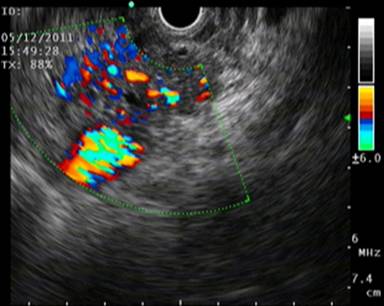

Figure 1. Endoscopic ultrasonographic image of the pancreatic arteriovenous malformation. |

CECT of the upper abdomen revealed bulky head and uncinate process of pancreas with altered attenuation and abnormal enhancement with multiple vascular channels within and around the head and uncinate process of pancreas with abnormal enhancement in adjacent wall of the duodenum and a cystic lesion in the head of the pancreas with haziness and stranding in the peripancreatic fat (Figure 2). Endoscopic ultrasound revealed multiple dilated vascular channels in the head of the pancreas (Figure 3) with portal vein thrombosis.